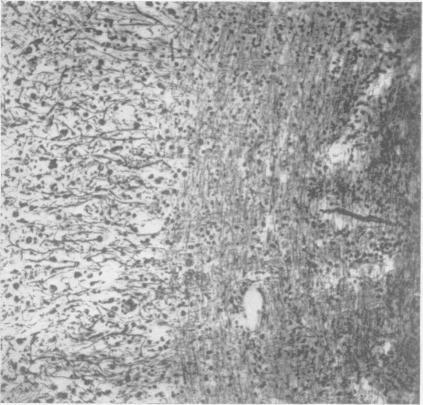

A benign tumour of the cerebellum; report on two cases of diffuse hypertrophy of the cerebellar cortex with a review of nine previously reported cases.

J Neurol Neurosurg Psychiatry. 1955 Aug;18(3):199-213. doi: 10.1136/jnnp.18.3.199.